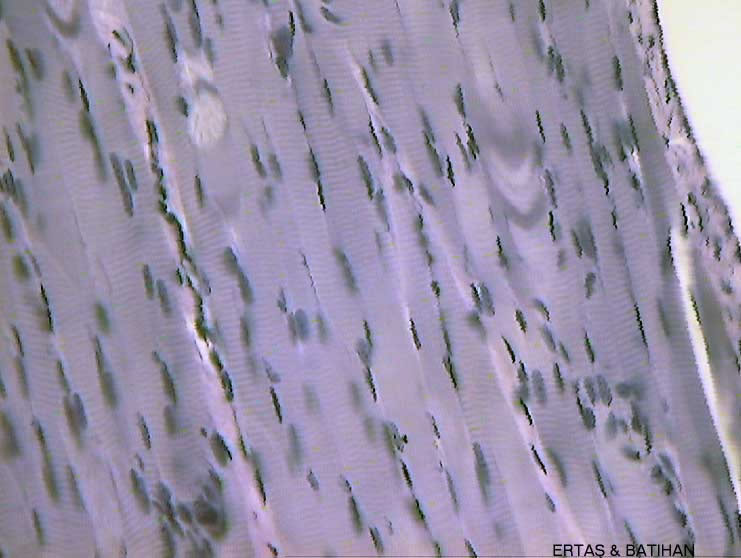

s/Skeletal-muscle-11-(40)(isk.jpg